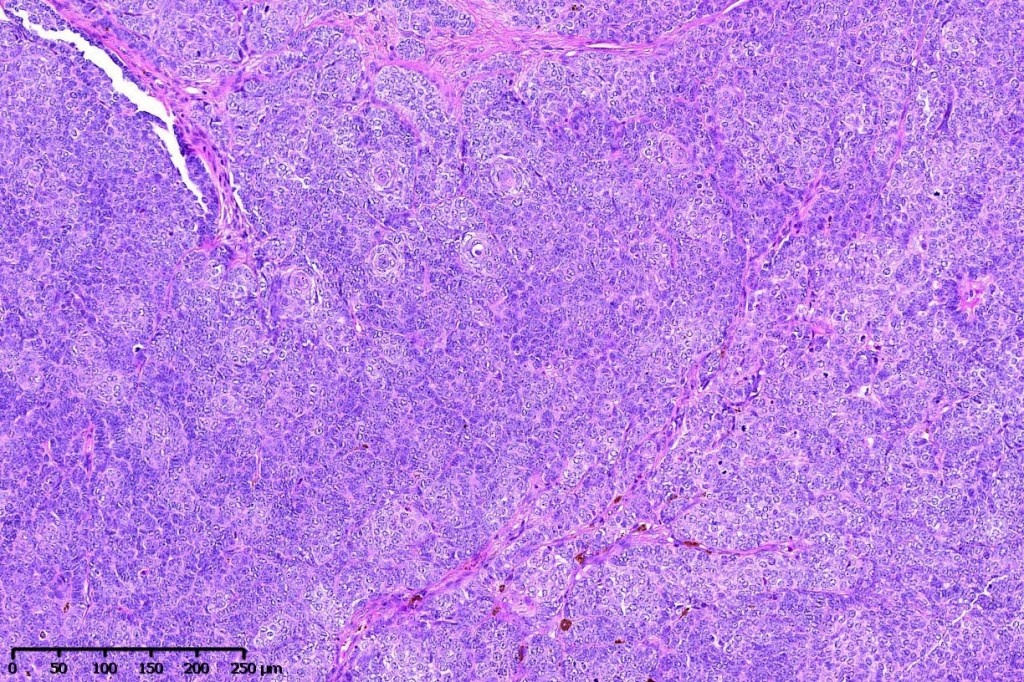

•Variably sized but generally large, basophilic tumor nodules composed of small uniform basaloid cells with minimal cytoplasm

•Variable mitotic activity, can be brisk

•No pleomorphism or abnormal mitoses

•Peripheral palisading but no retraction artifact or stromal mucin deposition

•A rich fibromyxoid mesenchymal stroma with variable papillary mesenchymal bodies (sometimes these are absent)

•Trichogerminoma is a distinctive variant being composed of tumor nodules with basaloid cells surrounding pale or eosinophilic micronodules (Zellballen)